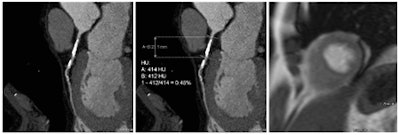

Coronary artery stenosis without hemodynamic significance: CCTA images are at left and center, while MRI (the reference standard for myocardial ischemia) is on the right. Images courtesy of Dr. Rozemarijn Vliegenthart."The results show that based on quantitative imaging biomarkers, derived from 'regular' coronary CT angiography, additional information can be gained regarding the hemodynamic significance of a coronary stenosis," Dr. Rozemarijn Vliegenthart wrote in an email to AuntMinnieEurope.com. "This is important because a large part of coronary narrowings with > 50% lumen diameter stenosis do not cause myocardial ischemia."